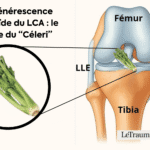

Arthrose du genou : douleurs à froid et la nuit

L’arthrose est la cause la plus fréquente. Elle touche 30 à 40 % des plus de 60 ans. La dégradation du cartilage provoque un frottement des os entre eux, surtout perceptible à froid, c’est-à-dire la nuit ou au réveil.

Lésions méniscales ou ligamentaires non traitées

Une lésion du ménisque, même ancienne, peut se réveiller en position allongée. Le genou devient douloureux lors d’un mouvement involontaire la nuit. Les douleurs ligamentaires post-traumatiques sont aussi fréquentes après une entorse mal soignée.